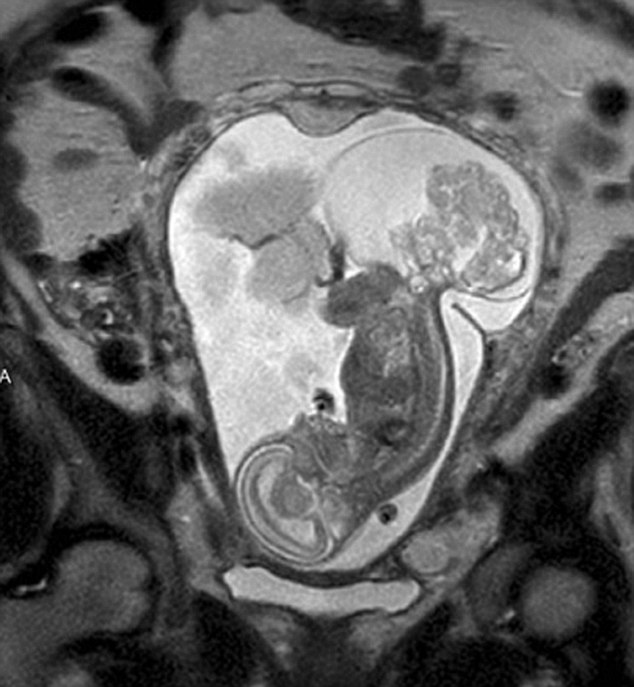

【環(huán)球網(wǎng)綜合報(bào)道】據(jù)英國(guó)《每日郵報(bào)》10月23日?qǐng)?bào)道,美國(guó)得克薩斯州布蘭諾市的女子瑪格麗特·伯默(Margaret Boemer)懷孕16周時(shí)去做產(chǎn)檢,不幸被告知胎兒尾骨上長(zhǎng)有腫瘤,她與醫(yī)生商量后決定先將胎兒取出進(jìn)行腫瘤切除手術(shù),再將其送回子宮繼續(xù)孕育。最終手術(shù)圓滿(mǎn)成功,12周后胎兒足月出生。

瑪格麗特稱(chēng)自己當(dāng)時(shí)聽(tīng)到產(chǎn)檢結(jié)果時(shí)十分害怕。“醫(yī)生說(shuō)寶寶長(zhǎng)了骶尾部畸胎瘤。我們很震驚,很害怕,因?yàn)槲覀兏静恢肋@個(gè)什么瘤到底意味著什么。”隨著時(shí)間流逝,腫瘤越來(lái)越大,胎兒滿(mǎn)23周時(shí)腫瘤已危及其性命。醫(yī)生告訴瑪格麗特,若想胎兒存活,只能將胎兒取出進(jìn)行手術(shù),然后再放回子宮,否則只能立即終止孕期。“這很容易做決定:讓腫瘤奪去孩子性命,或是給孩子存活的機(jī)會(huì)。我們當(dāng)然選擇后者。”瑪格麗特說(shuō)。

醫(yī)生將胎兒取出20分鐘后,便放回母體子宮。12周后,寶寶足月出生。瑪格麗特稱(chēng):“這可以說(shuō)是她的第二次出生了。只要她有機(jī)會(huì)活下來(lái),我愿意承受所有風(fēng)險(xiǎn)。”(實(shí)習(xí)編譯:高睿 審稿:朱盈庫(kù))